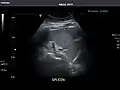

Ultrasound can also be used if there is suspicion of enlargement of one or more organs, such as used in screening for abdominal aortic aneurysm, investigation for splenomegaly or urinary retention.

In cases of infectious mononucleosis, splenomegaly is a common symptom, and health care providers may consider using abdominal ultrasonography to get insight into a person's condition.[5] However, because spleen size varies greatly, ultrasonography is not a valid technique for assessing spleen enlargement and should not be used in typical circumstances or to make routine decisions about fitness for playing sports.[5]

Spleen: Normal in size.